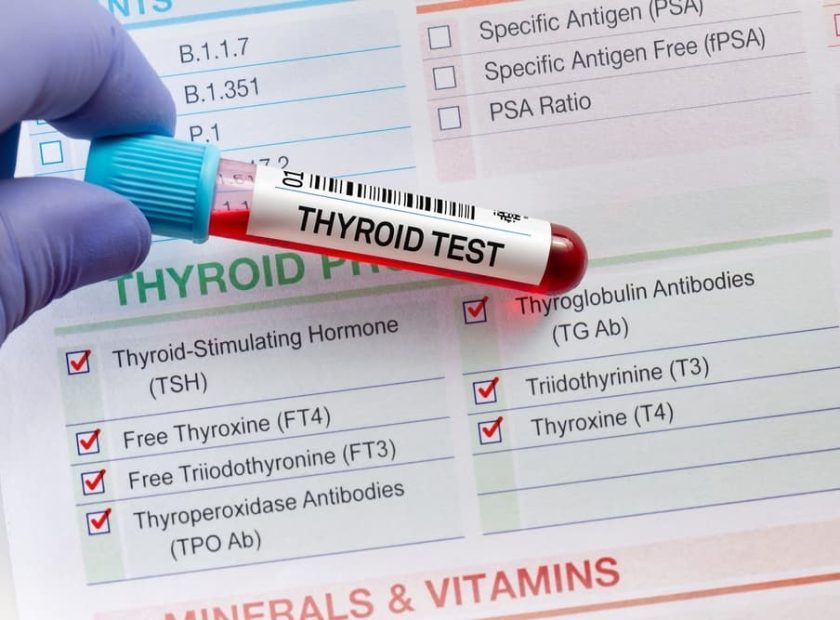

۷. تستهای عملکرد کبد و پانکراس (LFTs & Amylase)

اگرچه این اندامها مستقیماً “لوله” گوارشی نیستند، اما بدون آنزیمهای آنها، هضم در معده و روده مختل میشود.

- لیست موارد مورد بررسی:

- سطح آنزیمهای کبد (ALT, AST).

- سطح بیلیروبین (برای تشخیص زردی و انسداد مجاری صفراوی).

- آنزیمهای پانکراس (آمیلاز و لیپاز) برای تشخیص پانکراتیت.

- شرح آزمایش: این یک آزمایش خون ساده است که هماهنگی اندامهای جانبی با معده و روده را نشان میدهد. بسیاری از دردهای ناحیه فوقانی شکم که بیمار تصور میکند مربوط به معده است، در واقع ناشی از سنگ کیسه صفرا یا التهاب پانکراس است که در این تست مشخص میشود.

- شرایط پیش از آزمایش: برای دقت بیشتر در فاکتورهایی مثل بیلیروبین، ۸ تا ۱۲ ساعت ناشتایی توصیه میشود. مصرف الکل و برخی داروهای مسکن قبل از آزمایش باید متوقف شود.

تستهای عملکرد کبد و پانکراس